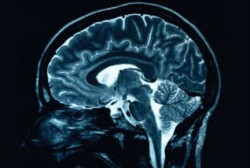

Le corps réel n’intéresse plus beaucoup la médecine qui lui préfère son transfert sur sa virtualité. Virtualité dont témoigne l’irruption de plus en plus exclusive des images et des chiffres. Ce qui surgit alors dans l’espace du réel ce n’est plus le corps dans sa violence relationnelle, son dépouillement, sa misère, ce sont des chiffres et des images numérisées. Images qui parlent du corps en le censurant puisquela plainte n’est plus recevable, tant qu’elle n’a pas de traduction objective technique. Échographie, scanner, endoscopie, doppler, dépistage des gènes ont confisqué peu à peu la relation soignante à leurs profits.

Le « su » du corps est remplacé par le « dit » de la médecine. Il n’est plus concevable qu’une douleur de la tête, du ventre, du thorax, du dos, de l’articulation ne justifie pas une demande d’imageried’imagerie. Son utilité est incontestable mais son usage incohérent et couteux crée les conditions d’un verdict négatif ou positif binaire. « La radio est normale, vous n’avez rien. » « La radio est pathologique, vous êtes malade », même si cette anormalité est parfois sans rapport avec la demande réelle de soin. Ce transfert quasi absolu de la parole du malade et de la main du médecin sur des images n’est pas sans conséquence. Un corps est une unité organique avant d’être une mosaïque de pixels. Mais l’instillation pernicieuse d’un principe de précaution dévoyé aboutit à ce que « on ne sait jamais » soit érigé en devoir d’investigations.

La médecine doit désormais s’appuyer sur des preuves. Or ces preuves ne seront jamais issues de l’examen du corps mais des chiffres biologiques et des images. L’observation clinique est contingente. La recherche clinique est effectuée sur des personnes standardisées. Elle impose ses valeurs au détriment du jugement clinique. L’idéal est celui des essais contrôlés randomisés, c’est-à-dire effectués dans l’ignorance du médicament prescrit par le médecin et par le malade pour ne pas influencer leur jugement. Cette modélisation, essentielle au progrès des connaissances, laisse le malade complexe, âgé, atteint de multiples pathologies hors champ. Car elle suppose un malade autonome sans relation avec le monde qui l’entoure, sans désir, ni sentiment ni contradiction interne.

Prédire le futur pour l’empêcher d’advenir peut sembler le comble de la prévention. Rompre l’enchaînement inéluctable du destin place la médecine en situation de pouvoir, d’autant plus que cette prédiction fondée sur des éléments techniques valorise scientifiquement la prévention. Un dos douloureux, qui le serait moins si la personne maintenait une musculature minimale, requerra une imagerie pourtant généralement impuissante à fournir une information utile. La prédiction d’une ostéoporose fournie par cette imagerie décrit les conditions de sa survenue douloureuse, puisque d’inconnue, elle est soudain devenue réelle sur l’image.